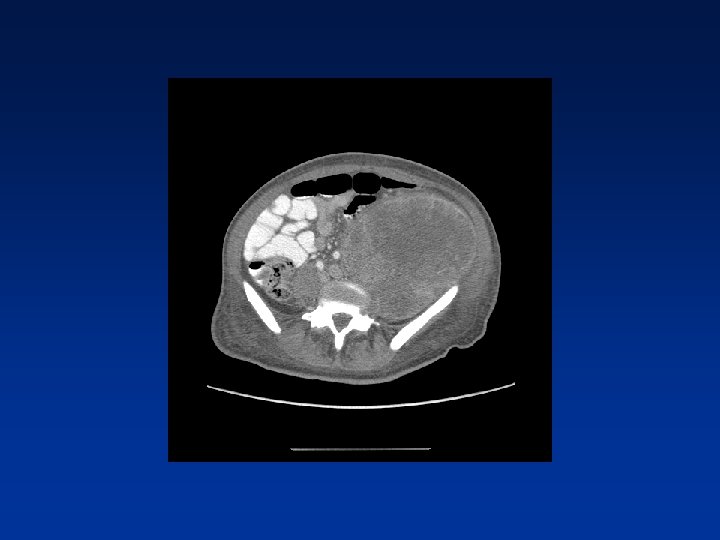

CASE